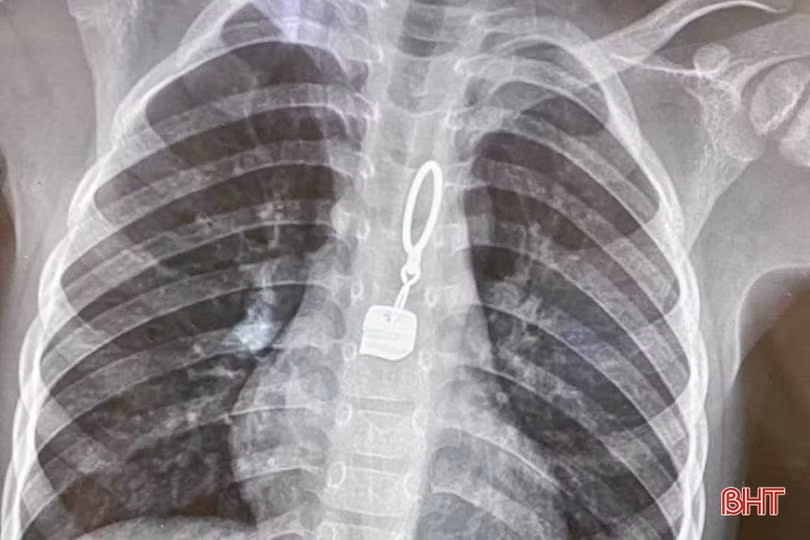

Hình ảnh dị vật trong thực quản của bệnh nhân.

Trước đó, tối ngày 4/1/2023, bé V.B.L (thị trấn Kỳ Đồng, huyện Kỳ Anh) có biểu hiện quấy khóc, đau họng. Sau đó, bé được gia đình đưa đến Trung tâm Y tế huyện Kỳ Anh thăm khám. Qua chụp chiếu, các bác sỹ phát hiện trong thực quản của bệnh nhi có dị vật nên đã nhanh chóng chuyển ra BVĐK tỉnh.

Khoảng hơn 10 phút, các y bác sỹ đã gắp thành công dị vật là một chiếc khoá áo ra khỏi thực quản. Sau khi dị vật được lấy ra, bệnh nhi không còn quấy khóc, đỡ mệt và được chuyển về Khoa Nhi tiếp tục theo dõi.